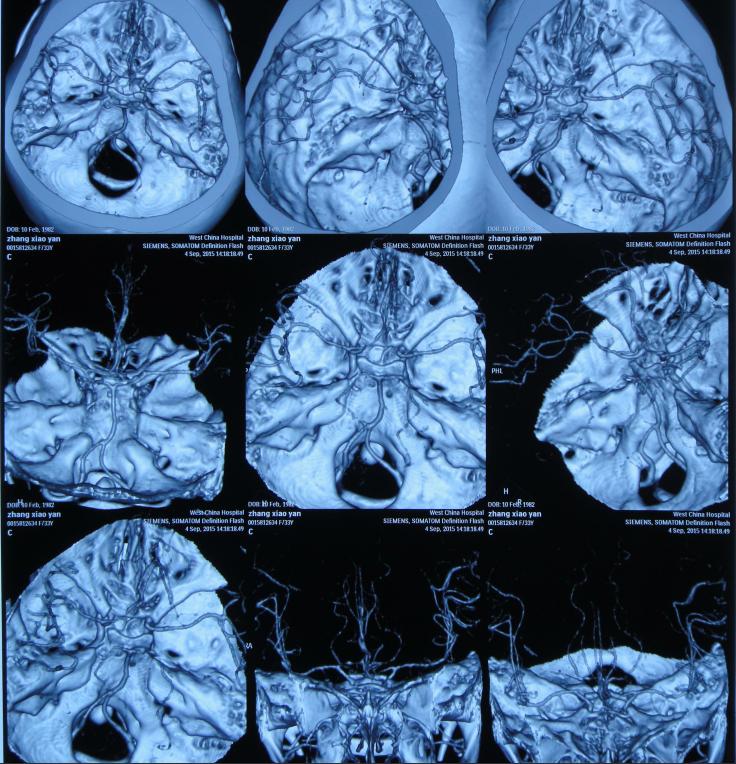

在第1家医院治疗32天后即2015年9月4日,为了进一步的治疗,转入上级的第2家我国西部著名的位于四川省成都市的某三甲医院的神经外科。查头部增强MRI示脑积水,感染性病变可能,结核,脑室系统扩张(图-6);头部CTA示脑积水,双侧基底节区多发低密度影,多系腔梗灶,颅内大血管未见明显异常(图-7);胸部CT:双下肺散在慢性炎症,双侧胸膜增厚,双侧胸腔少量积液(片子丢失)。

图-6:2015年9月4日头部CTA

图-7:2015年9月4日头部MRI增强